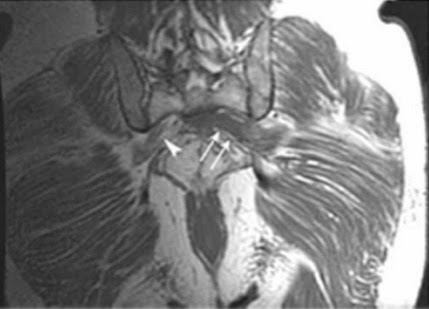

Imagen coronal 3D STIR muestra las raíces nerviosas del plexo sacro bilateral. Nervios femorales (puntas de flecha) y nervios ciáticos (flechas).